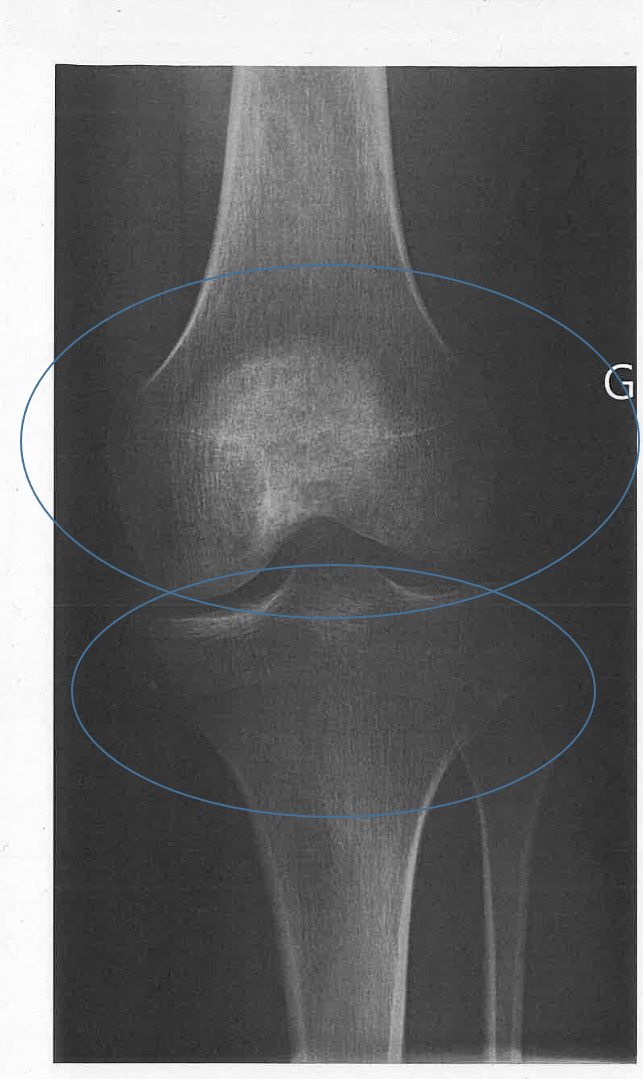

Un homme de 26 ans consulte pour un traumatisme du genou gauche survenu lors d’une chute à ski. Le bilan clinique retrouve une entorse du ligament collatéral médial, et l’imagerie par résonance magnétique objective un œdème médullaire postérieur du plateau tibial médial et un œdème médullaire antérieur du plateau tibial latéral.

Après deux mois, et malgré la rééducation, une impotence fonctionnelle se manifeste par un flessum à 15 ° du genou gauche, associé à des douleurs. La radiographie révèle des anomalies de la trame osseuse (fig. 1), évocatrices d’un syndrome douloureux régional complexe, confirmé par la scintigraphie osseuse (fig. 2).